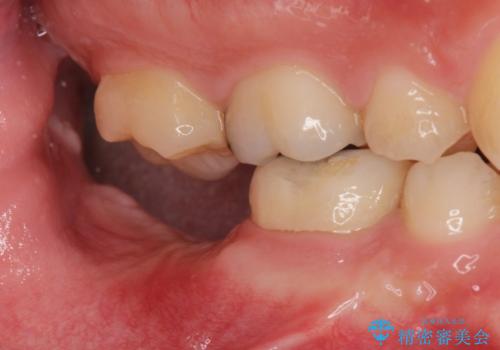

- 銀歯を白くしたいとのことで来院。

右下の被せ物を外し虫歯を除去したところ虫歯が深く保存が難しい状態だったので抜歯を行いました。

手前の銀の詰め物のところは除去して拡大鏡下で虫歯を取り除き、ジルコニアクラウンで治療を行いました。